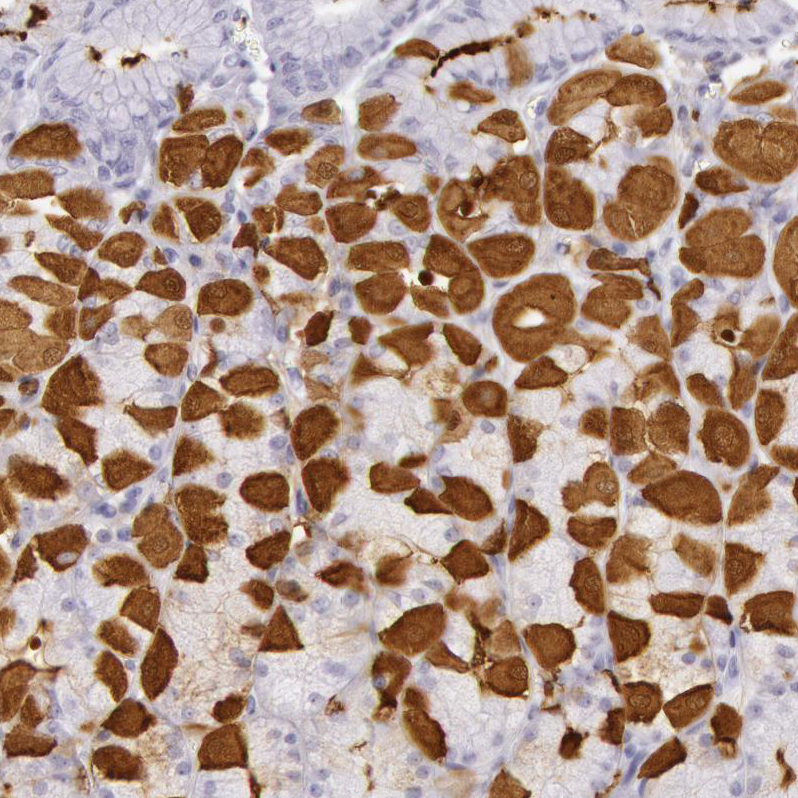

Immunohistochemistry analysis in human cerebral cortex and liver tissues using HPA001254 antibody. Corresponding CKB RNA-seq data are presented for the same tissues.